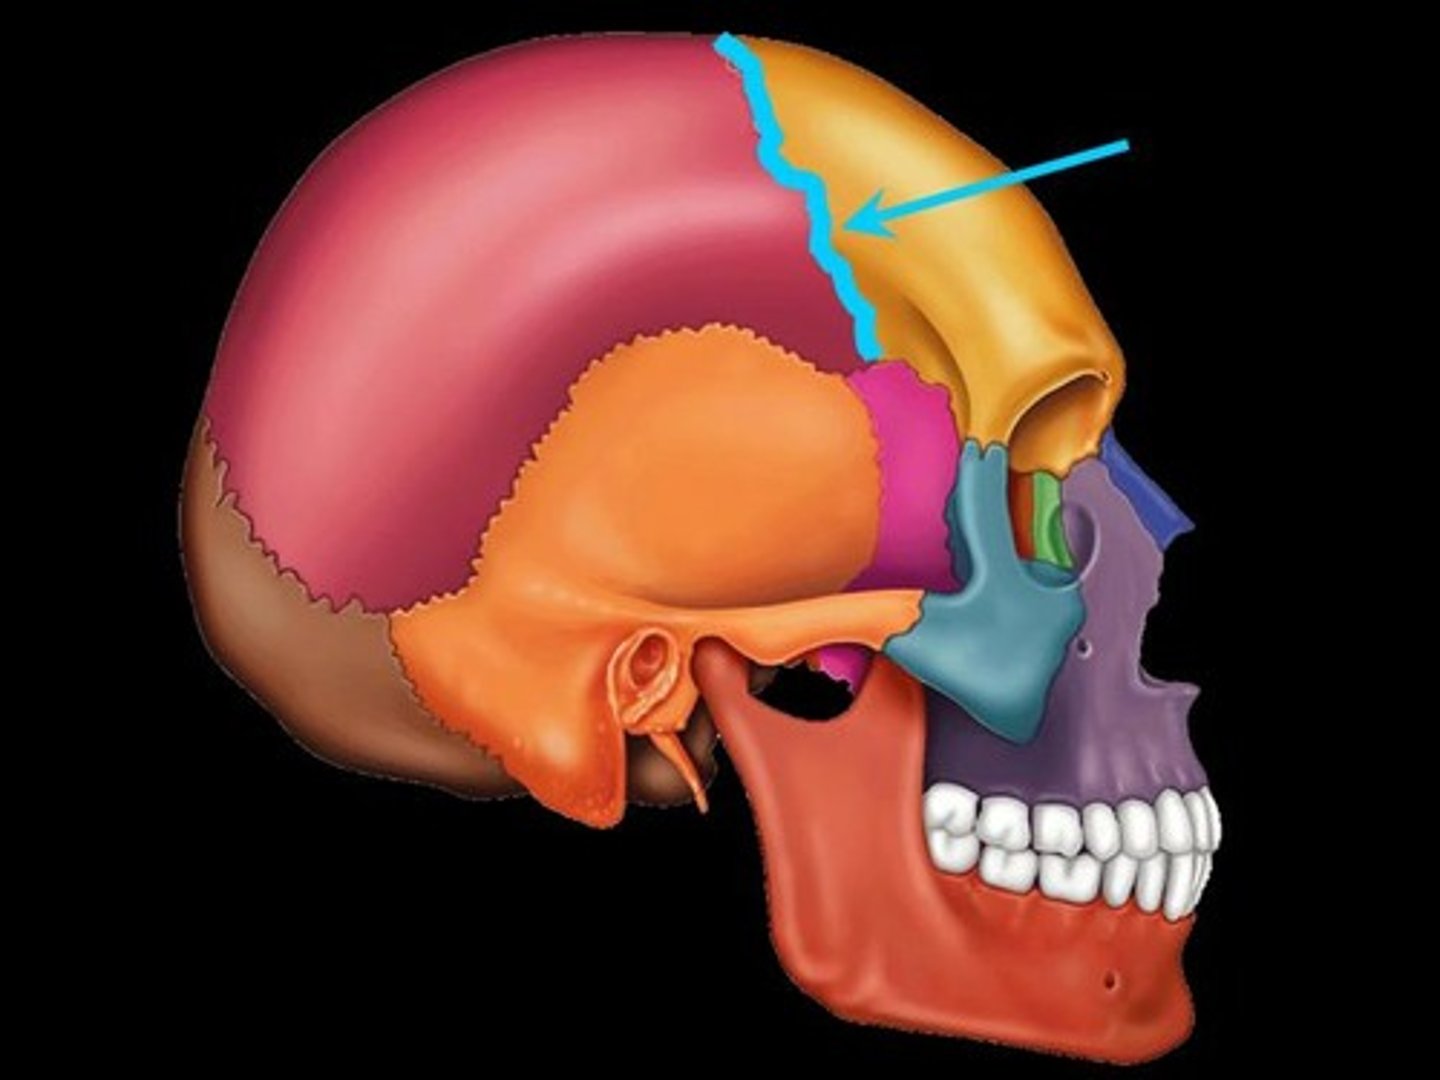

coronal suture

squamosal suture

pterion

frontal bone

parietal bone

sphenoid bone

temporal bone